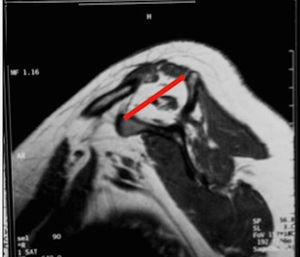

Clasificación de acuerdo con la calidad del tendónLa calidad del tendón se puede evaluar por TC o RM y su función principal es determinar si el tendón, por su calidad, es reparable. La clasificación más usada es la clasificación de Goutallier (tabla 5), basada en la existencia de infiltración grasa en imágenes de TC. Fuchs ha publicado también una clasificación similar con el uso de RM (figs. 3–6).